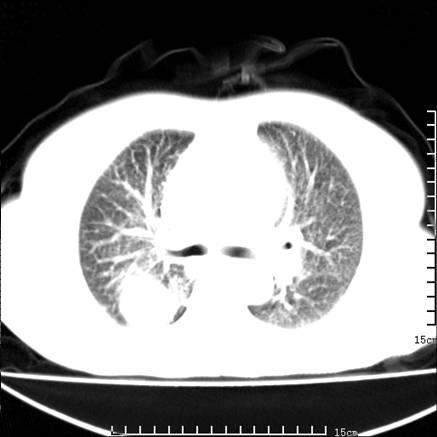

女,王某,58岁,咳嗽三个月余,基层医院二个月前诊为肺结核,用抗结核药二个月无明显疗效。

心包积液致肺瘀血.右侧周围型肺癌伴肺内转移,中间裂积液,叶间胸膜肥厚.右上肺大泡,右侧胸膜肥厚.

双肺继发型tb,心功能不全并肺淤血、心包、双侧叶间裂积液,肺大泡,右下胸膜肥厚钙化。